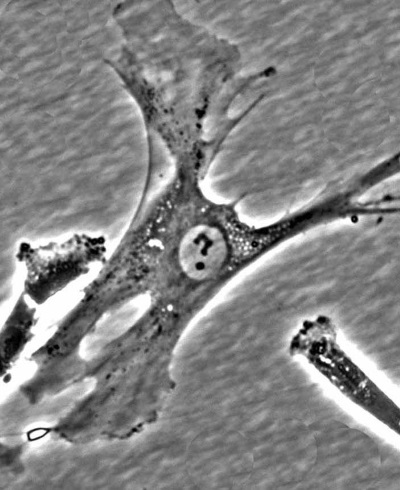

Это фотография живой мезенхимальной стволовой клетки, выделенной из костного мозга человека (фотография сделана автором статьи). Рядом с ней – отростки соседних клеток.

Это не монтаж! Это живая клетка. А знак вопроса – это хроматин (ДНК + белки) в ее ядре.

На следующий день эта клетка поделилась на две новые клетки.